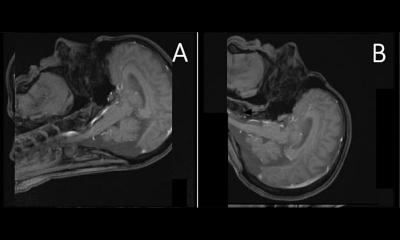

Mitglieder der Österreichischen Röntgengesellschaft, vertreten durch Grazer Kinderradiologen, sind bei Dosis und Dosismonitoring an zwei wichtigen Projekten beteiligt: „EC Tender PiDRL – European Diagnostic Reference Levels for Paediatric Imaging“ und elektronischer Strahlenpass (eStrahlenpass: „Patient Leading and Manageing their Healthcare through eHealth“). In dem PiDRL-Projekt sollen auf europäischer Ebene verbindliche und adäquate DRLs für bildgebende Untersuchungen bei Kindern definiert werden. Dabei ist große Sorgfalt auf die Altersabstimmung zu legen, da sich die Strahlenbelastung bei Kindern mit dem Alter ändert. So ist die relative Strahlenempfindlichkeit des Kopfes bei Kindern etwa 3,5 mal höher als bei Erwachsenen, während sich dies bei den Gonaden umgekehrt verhält. Beide Phänomene lassen sich durch die Entwicklung und Reifung des Kindes erklären. PiDRL ist Teil von „ESR Eurosafe Imaging“ – einer neue Initiative für mehr Patientensicherheit.